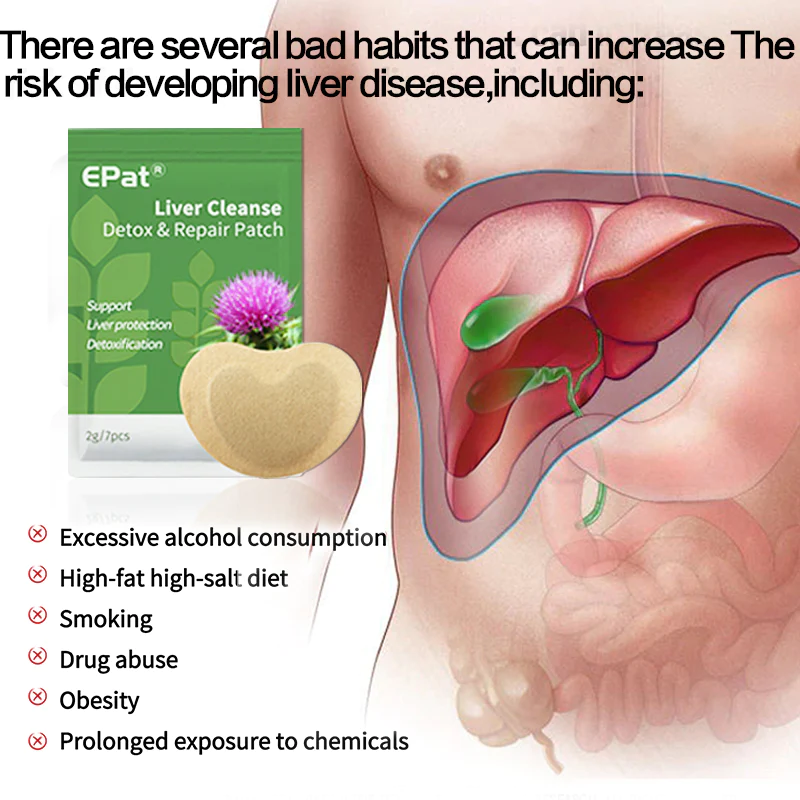

EPat® Liver Cleanse Detox & Repair Patch는 Dr. Shannon Deleon의 연구팀에 의해 만들어졌으며 식물 추출물로만 만들어진 혁신적인 비건 포뮬러를 사용합니다. 그 목적은 간의 정상적인 기능을 복구 및 복원하여 신체가 단 XNUMX주 내에 해독 능력을 향상시킬 수 있도록 하는 것입니다. 또한 과도한 간 지방을 제거하고 간 세포의 재생을 촉진할 수 있습니다.

EPat® Liver Cleanse Detox & Repair Patch는 어떻게 작용합니까?

- 제품은 피부를 통해 직접 흡수되어 모세혈관 흡수를 통해 혈액순환에 들어가 간에 작용하여 간 해독 및 간 조직 재생을 촉진합니다. 일반 간 해독제에 비해 이 방법은 약보다 63% 더 높은 해독 및 간장강화 효과가 있습니다.